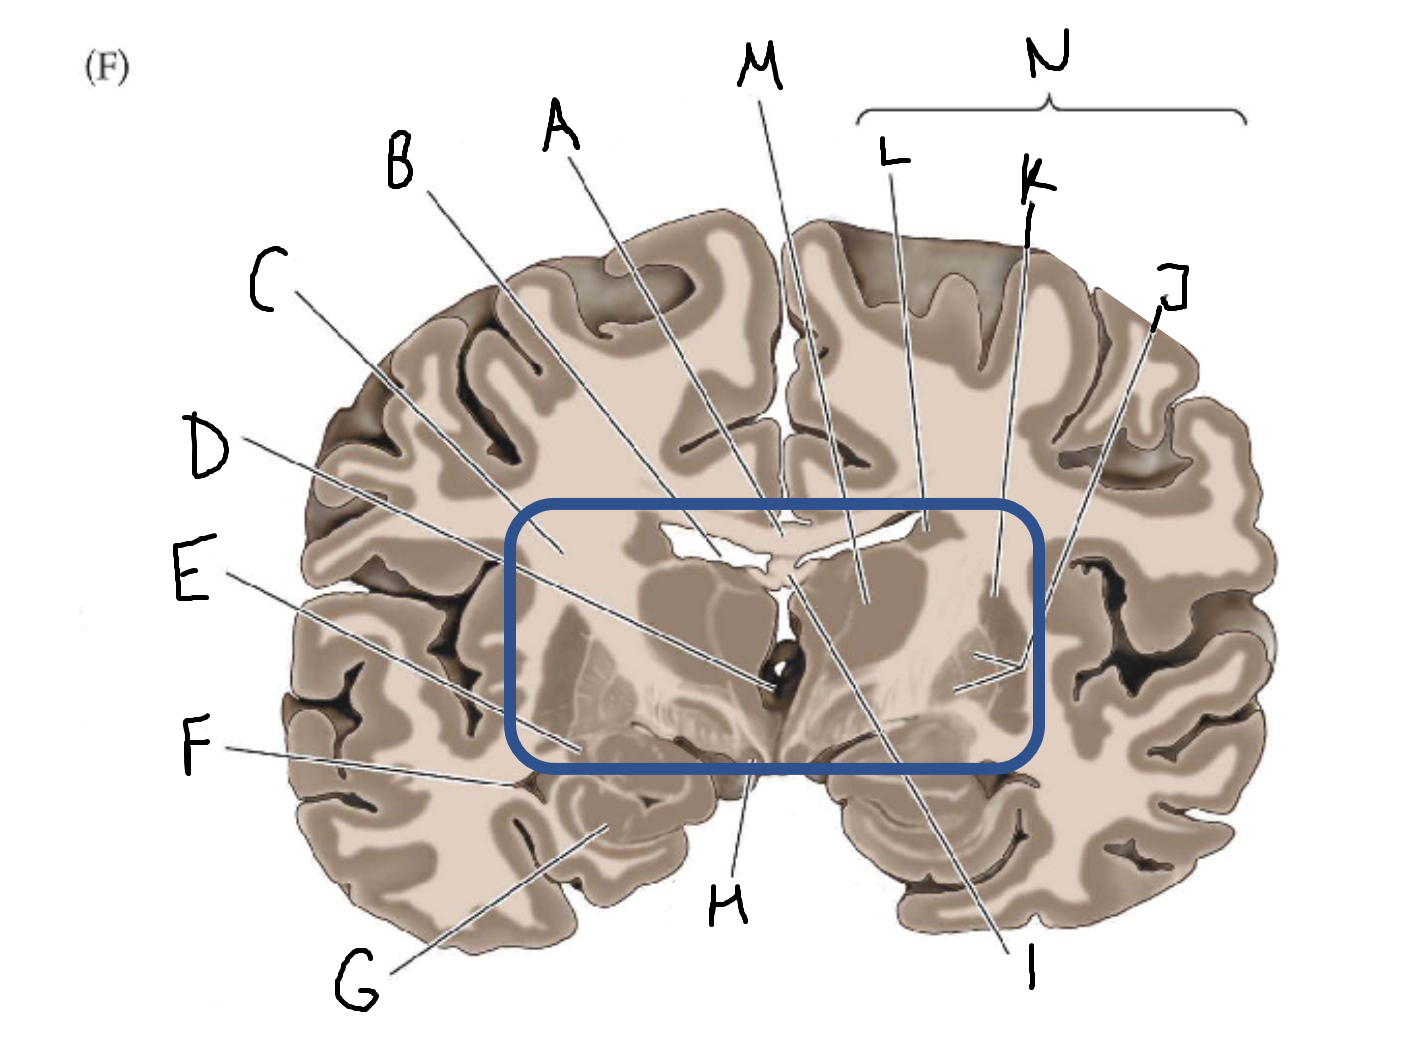

A

corpus callosum

B

lateral ventricle

C

internal capsule

D

third ventricle

E

tail of caudate nucleus

F

lateral ventricle

G

hippocampus

H

mammillary body

I

fornix

J

globus pallidus

K

putamen

L

caudate

M

thalamus

N

basal ganglia